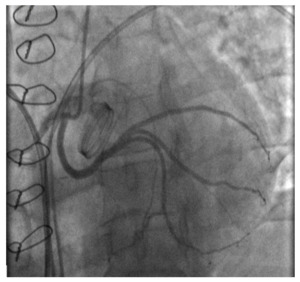

Postoperative coronary angiography revealed a patent LCx without compression by the prosthetic valve (Fig.3). Control echocardiography showed no significant changes in the size and contractility of the LV; there was a moderate regression of LV hypertrophy compared to preoperative data, and a normally functioning mechanical aortic prosthetic (a peak gradient of 20.1 mmHg, a peak acceleration of blood flow of 2.2 m/s). The postoperative course was uneventful.